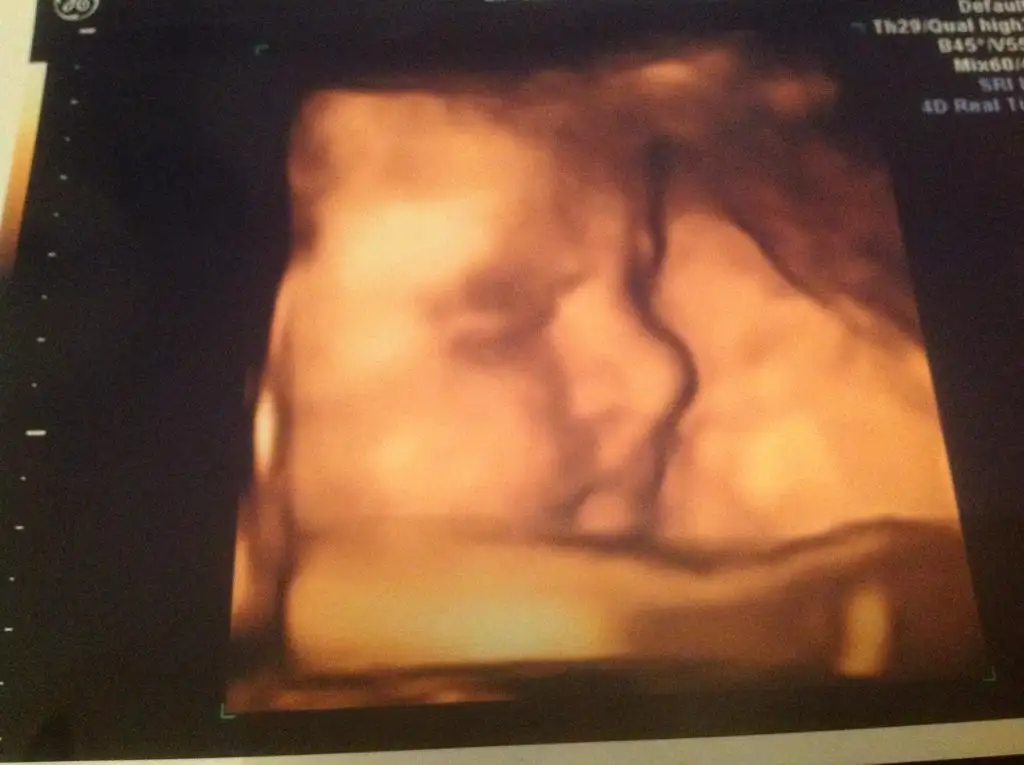

Biz kızımla iyiyiz çok şükür.Artık eğilmekte sıkıntı çekiyorumAğırlaşmalar başladı.Afra hanım her zaman ki gibi oldukça kıpraşık :)) Şeker yüklememizde sorun çıkmadı neyseki.

Boyumuz kilomuz oldukça iyi.3+4 gün ilerde gelişmesi.Afra hanımdan bu sefer görüntü alabildik :)

ayyyyyyyy kuzucum benım bıtanem kocaman olmuş maşallaha süpanallah

kuzucum dudaklarını burnunu yerim ben onun yaaaa cok duygulandım

nerden nereye daha dün gibi her ay bu sürprizi beklıyordun mınıcıktı hayal gibiydi buyudü kocaman oldu prensesım hatta oğlan bıle sanmıştık aframızı rabbım sağlıkla kucağına versin bak bıttı bıle kuzucum herşey cok güzel olacak ona anlatacağın cok güzel anıların olacak ınş. nasılda aylarca bekledin anlatacaksın kızına